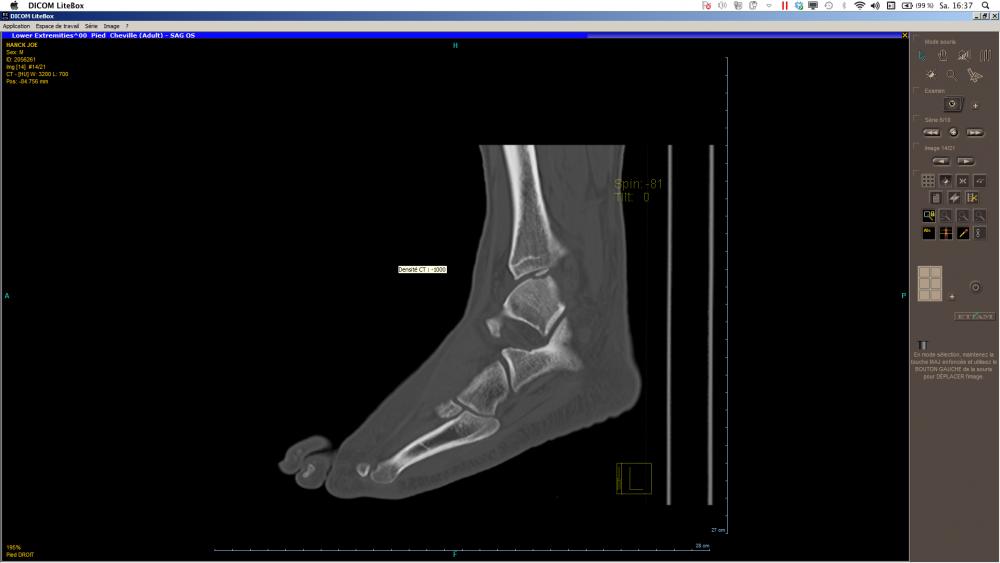

Die Osteochondrosis dissecans (kurz OCD bzw. OD, angloamerikanisch auch Osteochondritis dissecans) ist eine umschriebene Knochenläsion unterhalb des Gelenkknorpels, die im ungünstigen Fall mit einer Separation und Abstoßung des betroffenen Knochenareals mit dem darüberliegenden Knorpel als freier Gelenkkörper (Gelenkmaus) enden kann. Es verbleibt dann ein Gelenkflächendefekt (Mausbett). Es besteht aber auch die Möglichkeit einer spontanen Ausheilung oder ein Ausheilung unter therapeutischen Maßnahmen. Es handelt sich nicht um eine primäre Knochennekrose, sondern um die Folgen einer Chondronekrose in der sekundären Physe (s. u.) Die OCD kann die meisten großen Gelenke des menschlichen Körpers betreffen, sie tritt aber vor allem im Kniegelenk, im oberen Sprunggelenk und im Ellbogengelenk auf. Aufgrund konzentrierter mechanischer Einwirkung tritt die OD jedoch fast ausschließlich in konvexen Gelenkanteilen wie dem Femurkondylus, der Talusrolle, dem Condylus radialis des Humerus und am Femurkopf auf. Die klassische Osteochondrosis dissecans kommt bei Kindern und Jugendlichen vor, da für die Entstehung noch offene Wachstumsfugen die entscheidende Voraussetzung sind. OCD bei Erwachsenen ist keine separate Erkrankung, sondern eine Form, die im Jugendalter nicht erkannt wurde, weil sie möglicherweise symptomarm verlief. Dieser Artikel orientiert sich vor allem an der Lokalisation Knie. In der Veterinärmedizin kommt sie insbesondere bei großen Hunderassen (Schulter, Ellbogen, Knie, Sprunggelenk etc.) und bei Mastschweinen vor. Inwieweit osteochondrale Ablösungen in Gelenken (Chips) bei Pferden dem gleichen Pathomechanismus unterliegen, bleibt zu klären.

Ist der betroffene Bereich noch nicht abgelöst, aber eine beginnende Abgrenzung durch gelbliche Verfärbung oder Knorpelaufwerfung an den Rändern oder eine für den Tasthaken einsehbare Fissur erkennbar, kann man durch einen Bohrkanal eine retrograde Spongiosaplastik oder durch den abgehobenen Befund (Knorpel-Knochen-Deckel) eine offene Knochentransplantation und zusätzlich eine Bohrung in der Basis des Befundes durchführen. Dieses Verfahren findet besonders bei den hartnäckigen Befunden am Sprungbein (Talus) Anwendung, die selten spontan ausheilen. Die Bohrung kann bei solchen Befunden sehr zielgenau durch den Gelenkknorpel hindurch (transchondrale Bohrung) durchgeführt werden.